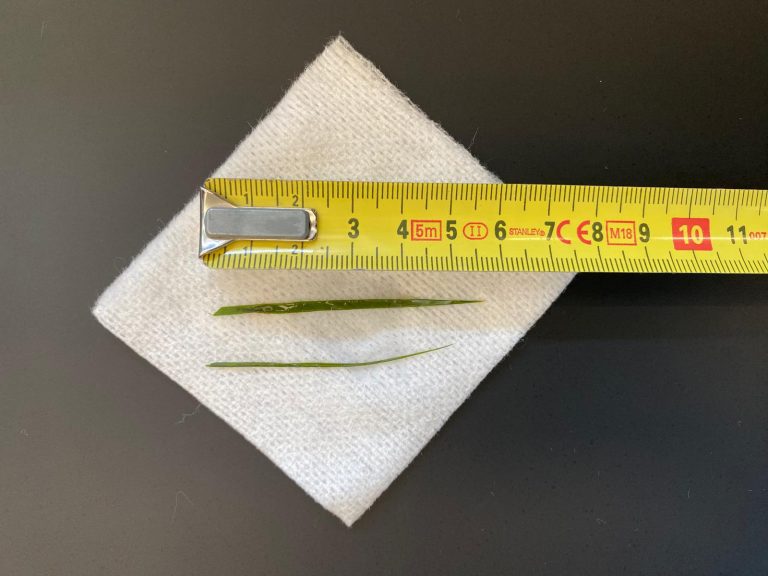

Er zijn speciale plastic Katkor kattenbakkorreltjes te verkrijgen aan de balie, met een pipetje en een buisje. Ons advies is om de kat een nachtje op te sluiten met een schone, lege kattenbak met alleen de speciale korrels erin. Meestal lukt het om vervolgens de urine hieruit op te zuigen en langs te brengen voor onderzoek. Indien het niet lukt om het direct langs te brengen, dan kan het enkele uren in de koelkast bewaard blijven. Overleg altijd even met de assistente aan de balie of het nut heeft om de opgevangen urine in te leveren, indien het een langere tijd heeft gestaan.

Mocht het echt onmogelijk zijn om op deze manier urine op te vangen, bijvoorbeeld omdat de kat het hele huis bij elkaar blèrt of de huisraad en de deur sloopt, dan kunnen we hem of haar ook een nachtje op de praktijk opnemen. Hierbij krijgt de kat een plekje in onze kattenopname, met voer, water en een kattenbak met Katkor. Er wordt geen dekentje verstrekt, omdat katten graag daarop plassen.

En uitgewrongen urine kunnen we helaas niet gebruiken. Soms kunnen ze het dan ineens verbazend lang ophouden en kan het wel twee dagen duren voordat de kat daadwerkelijk geplast heeft.